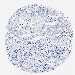

CANCER BREAST CANCER Show tissue menu

BRCA TCGA BRCA VALIDATION PROTEIN EXPRESSION